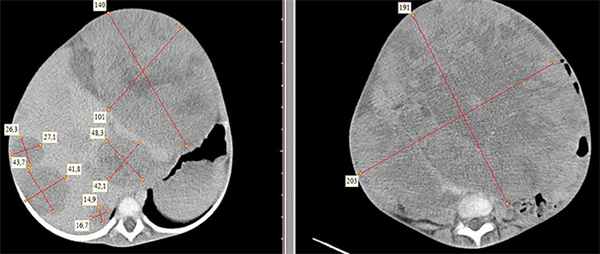

Рисунок 1. КТ брюшной полости ребенка с большой нефробластомой с метастазами в печень.

Рисунок 2. КТ: опухоль при поступлении. Клинически: при пальпации опухоль в проекции правой почки до 12 см в диаметре. Общеклинические исследования в пределах возрастной нормы. При КТ органов брюшной и грудной полости: КТ-картина объемного образования правой почки без признаков интрапульмональных метастазов (см. рис. 2). УЗИ брюшной полости: в проекции правой почки солидно-кистозное образование 101ґ114ґ99 мм, объемом 500 мл, васкуляризация активная, интактная часть почки 57ґ12ґ40 мм. Объемное образование правой почки — опухоль Вильмса. Предварительный диагноз: опухоль Вильмса правой почки, 2-я стадия.

Рисунок 3. Контрольная КТ: опухоль после предоперационной химиотерапии. Ребенку проведена предоперационная химиотерапия. На 5-й неделе лечения КТ-контроль показал уменьшение опухоли в размерах до 90ґ80ґ100 мм (см. рис. 3).